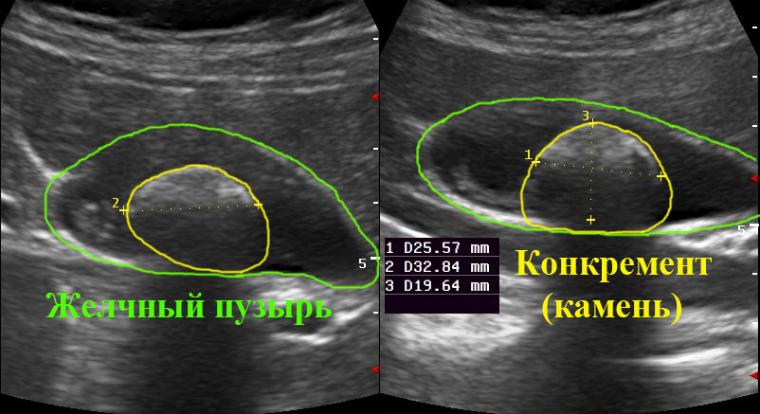

Основным методом диагностики этого недуга является УЗИ – ультразвуковое исследование желчного пузыря. Эта диагностическая методика позволяет не только обнаружить присутствие в полости пузыря конкрементов, но также определить их размеры, количество и места локализации, а также по утолщению стенок органа выяснить наличие сопутствующего воспалительного процесса.